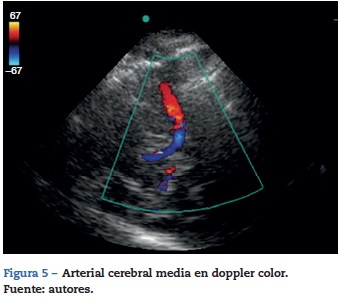

Parte de lo anterior puede sobrepasarse si se realiza un doppler trascraneano añadiendo la función color; se requiere un ultrasonógrafo con un transductor microconvex de 1 a 5 Mhz y software con función doppler y color. La ventana ultrasono-gráfica se obtiene a través de la escama del hueso temporal (fig. 5). Una segunda ventana puede realizarse a través del ojo para encontrar la arteria oftálmica, yuna tercera ventana a través de la región postauricular para acceder a la arteria cerebral posterior. La adición de la función color posibilita la visualiza-ción de las arterias intracraneales, especialmente la arteria cerebral media38 (fig. 5).

Las dos aplicaciones más aceptadas del doppler tras-craneano son control de vasoespasmo en pacientes con hemorragia subaracnoidea (evidencia clase IIa)16,38-47 y el apoyo del diagnóstico de muerte cerebral (evidencia IIa)39-48. Otras aplicaciones pero aún con evidencia limitada son el neu-romonitoreo a través de velocidades de flujo en las principales arterias cerebrales, en el que se pretende monitorizar la hemodinámica cerebral42-45. Se ha propuesto la evaluación de la integridad de la autorregulación cerebral a través de la relación del flujo de la arteria cerebral media y sus velocidades medidas por doppler con la presión arterial media46.

Ha sido de interés en cuidado neurocrítico y para neu-roanestesiología la posibilidad de tener un neuromonitoreo de pacientes críticos en unidades de cuidados intensivos o en salas de cirugía. El doppler trascraneano color tiene un potencial invaluable como herramienta que proporciona información dinámica, en tiempo real y no invasiva sobre variables manipulables de la hemodinámica cerebral y que potencial-mente impactan en el desenlace final de los pacientes49,50.